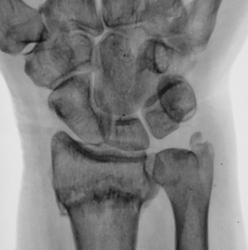

Травма. направлен на рентгенографию лучезапястного сустава

Сколько дней этому перелому?

Судя по карточке и записям в ней, перелом "от вчера".

Края отломков несколько заокруглены. Слабо намечается костная мозоль в лучевой кости.Видимо, пациент врет о дате травмы.

Перелому как минимум 2-3 недели.

Мне тоже " кажется", что с крючковидной костью " что- то не так". Не исключается хроническая травма, вплоть до востановления после асептического некроза?! Осеохондропатии??? По поводу перелома- скорее несвежий , более 1нед.

Поперечный перелом луча в типичном месте с разгибательной (сколько-то градусов) деформацией оси, боковым смещением на ширину кортикала, захождением ≈ 4 мм, перелом ШОЛК с/с.

Для оценки кистовидно измененной полулунной кости и исключения "дыр" в основании 4 пястной кости... укладку и центровку на кисть - и картина, возможно, поменяется)).